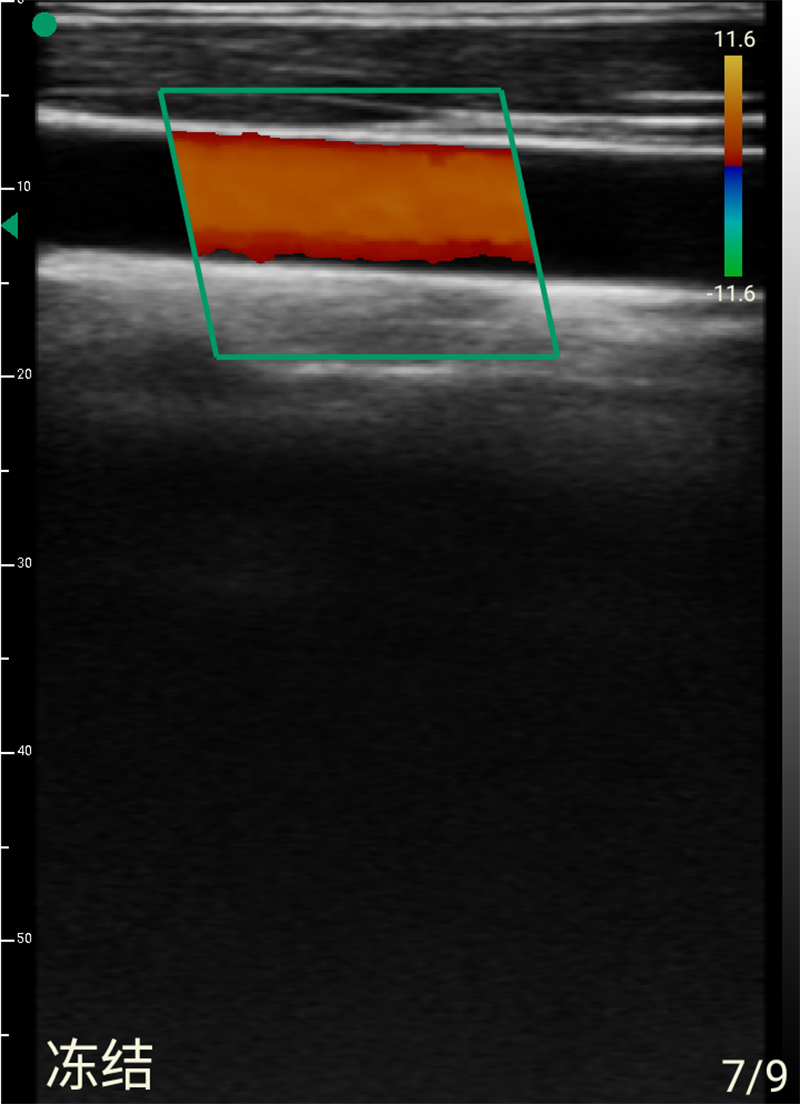

- Display mode: B, B/M, B+Color, B+PDI, B+PW

- Probe frequency: Linear 7.5MHz/10MHz

- Scan depth: Linear 20/30/40/55mm

- Scan width: Linear 40mm